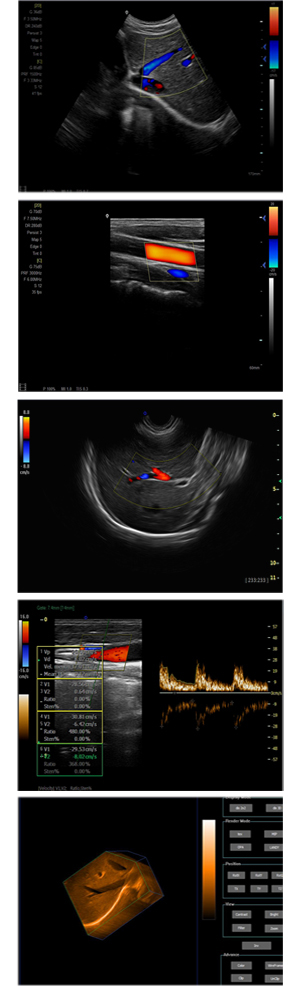

為高集成數字式彩色多普勒系列產品之一,廣泛實施于腹部,產科,婦科,血管,小器官,泌尿,新生兒和兒科等臨床,屬全身應用型彩色多普勒儀器。

●全身應用型包含2D/CFM/PDI/PW/ M等掃描模式;

●升級版可選配3D、反向諧波等高級功能。